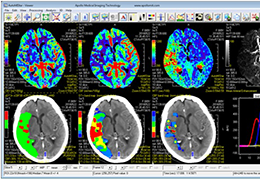

ANYTHINK 经导管主动脉瓣膜置换术分析系统